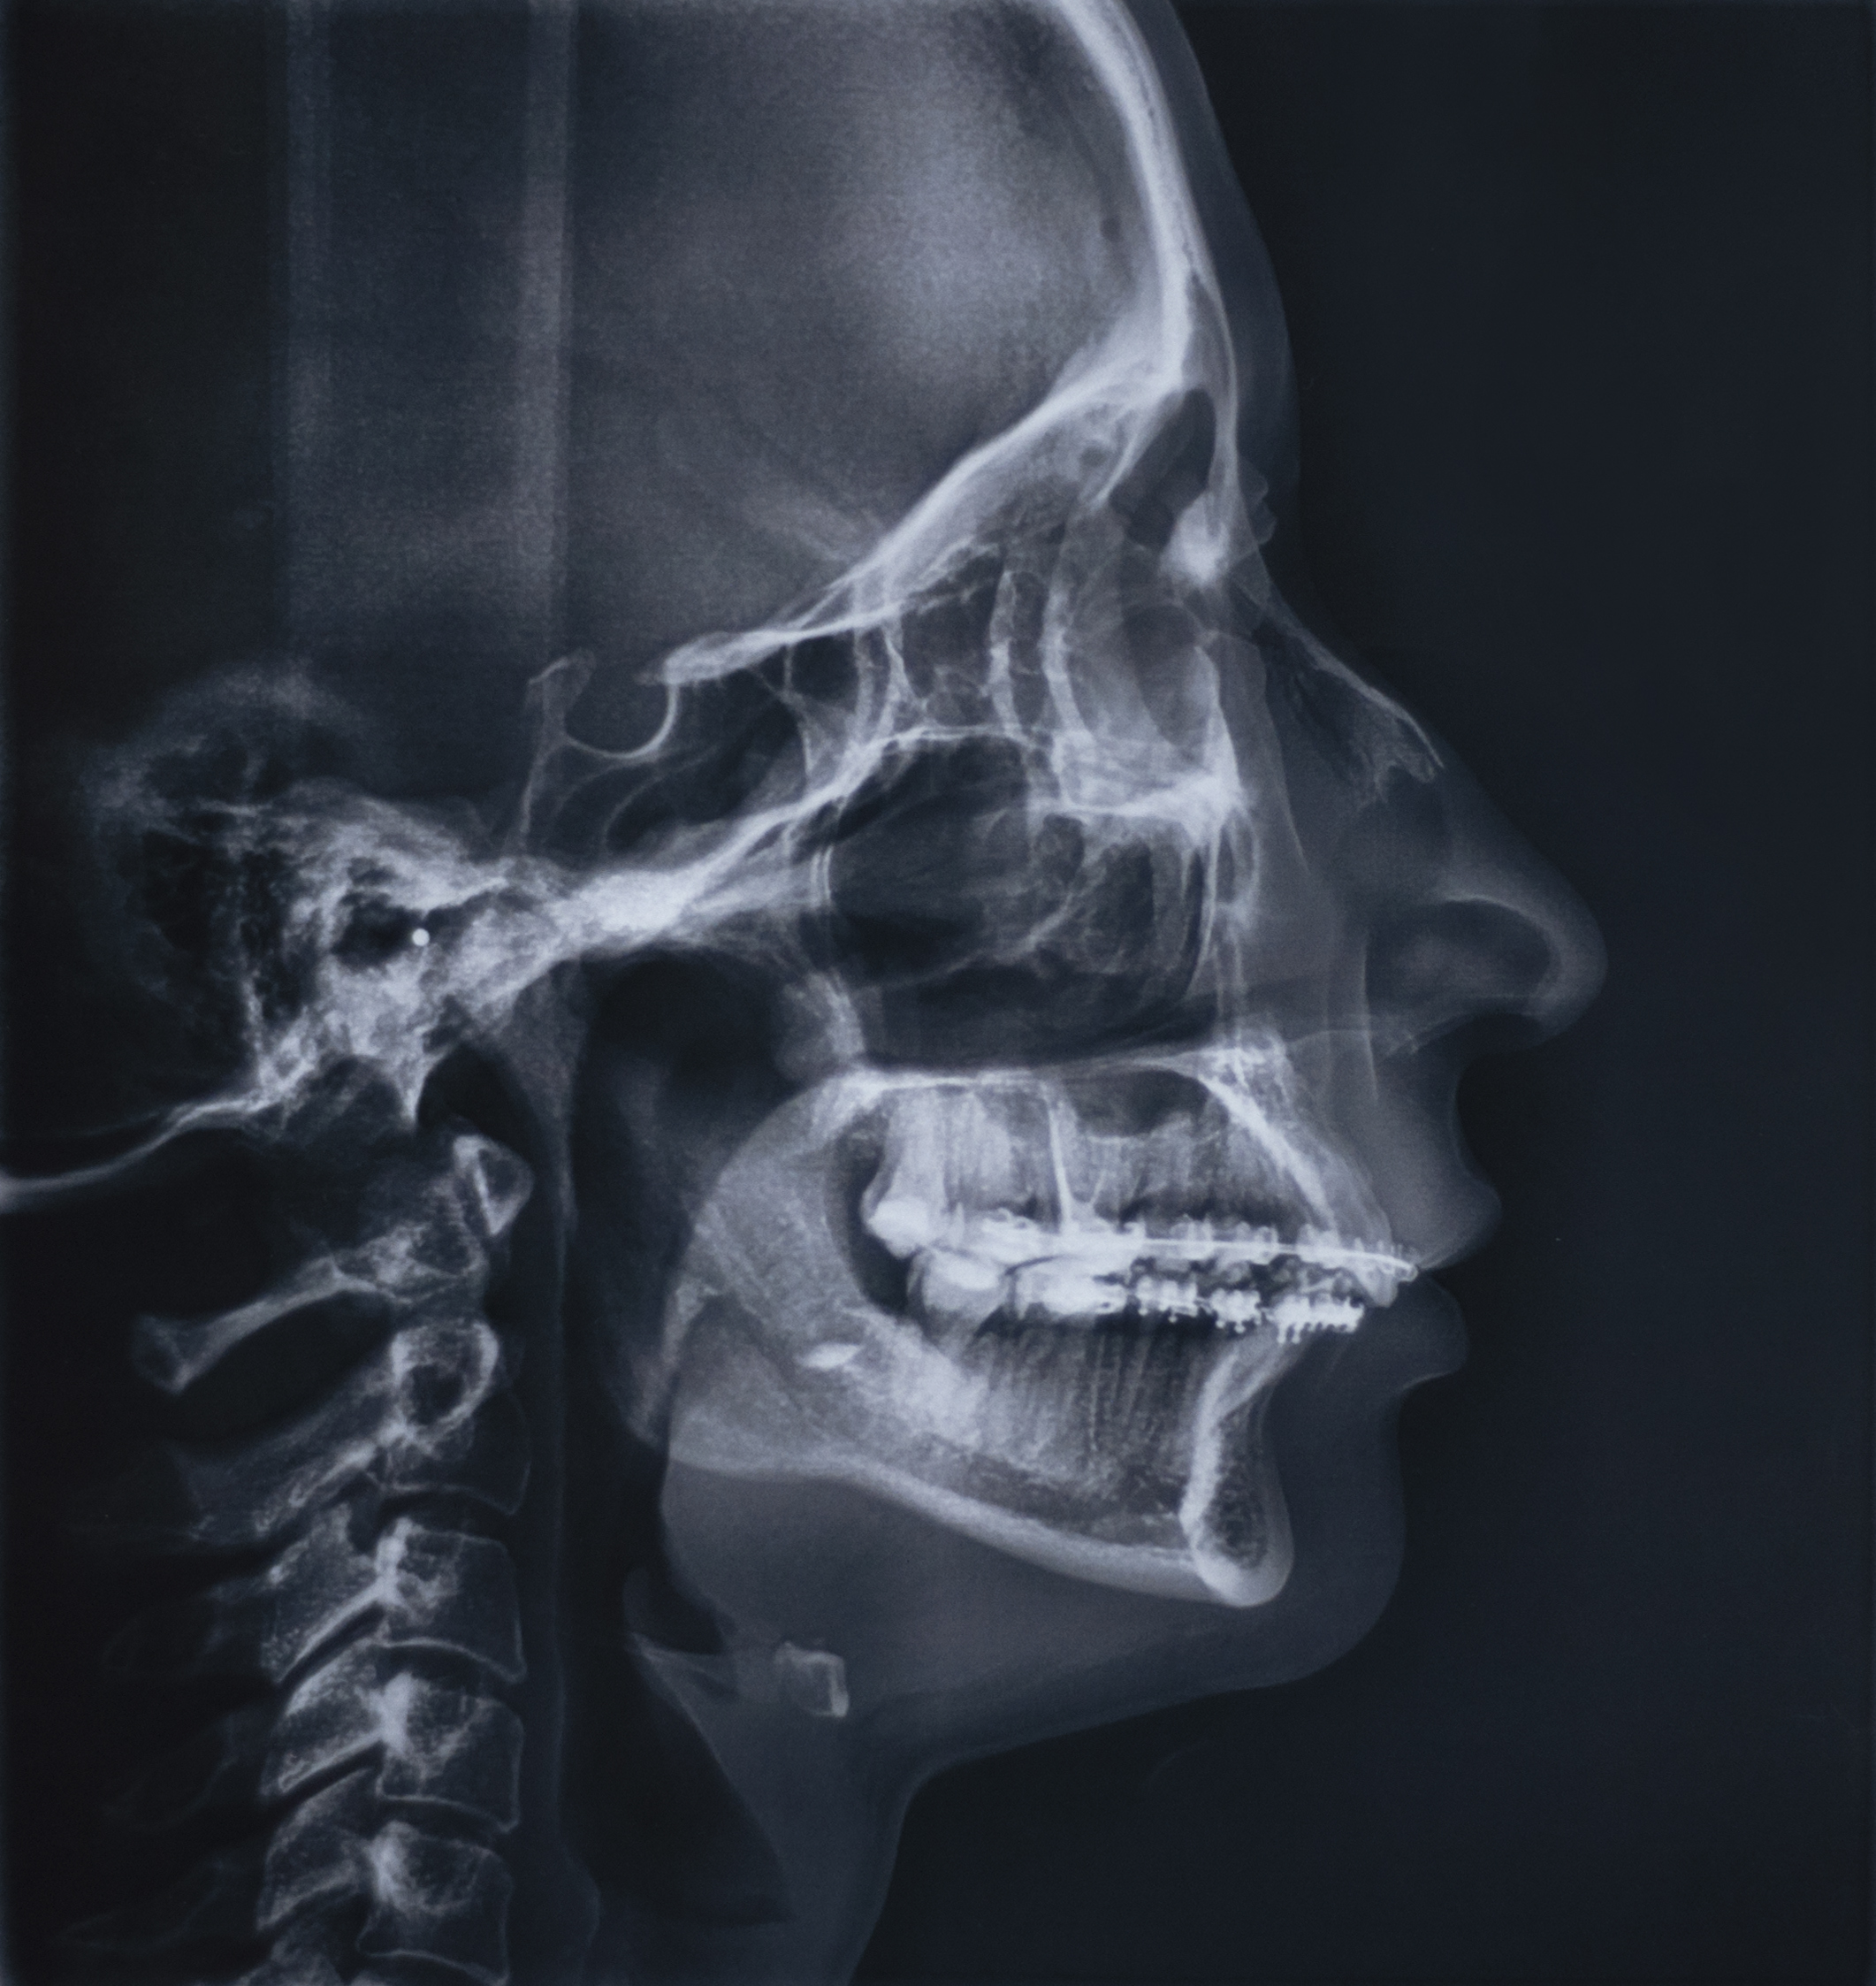

At its core, a cephalometric X-ray is a specialized type of radiographic image that captures a side view of the head, showcasing the bones, teeth, and facial contours. Derived from the Greek words "kephalē" meaning head and "metron" meaning measure, cephalometry involves the precise measurement of these structures to aid in diagnosis and treatment planning.

Unlike standard dental X-rays that focus on specific areas like individual teeth or the jawline, cephalometric X-rays offer a holistic view, providing invaluable insights into spatial relationships within the craniofacial complex.

Dentists and orthodontists analyze cephalometric X-rays by identifying specific anatomical landmarks and taking precise measurements:

- Nasion (N): The midpoint where the frontal and nasal bones intersect.

- Sella (S): The center of the pituitary fossa within the sphenoid bone.

- Point A and Point B: Key points on the maxilla and mandible, respectively, used to assess jaw relationships.

- Gonion (Go): The angle point of the mandible.

- Frankfort Horizontal Plane: An imaginary line used as a reference for craniofacial angles.